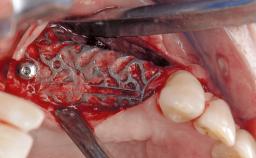

Treatment of Peri-Implant Mucositis at a Zirconia Implant